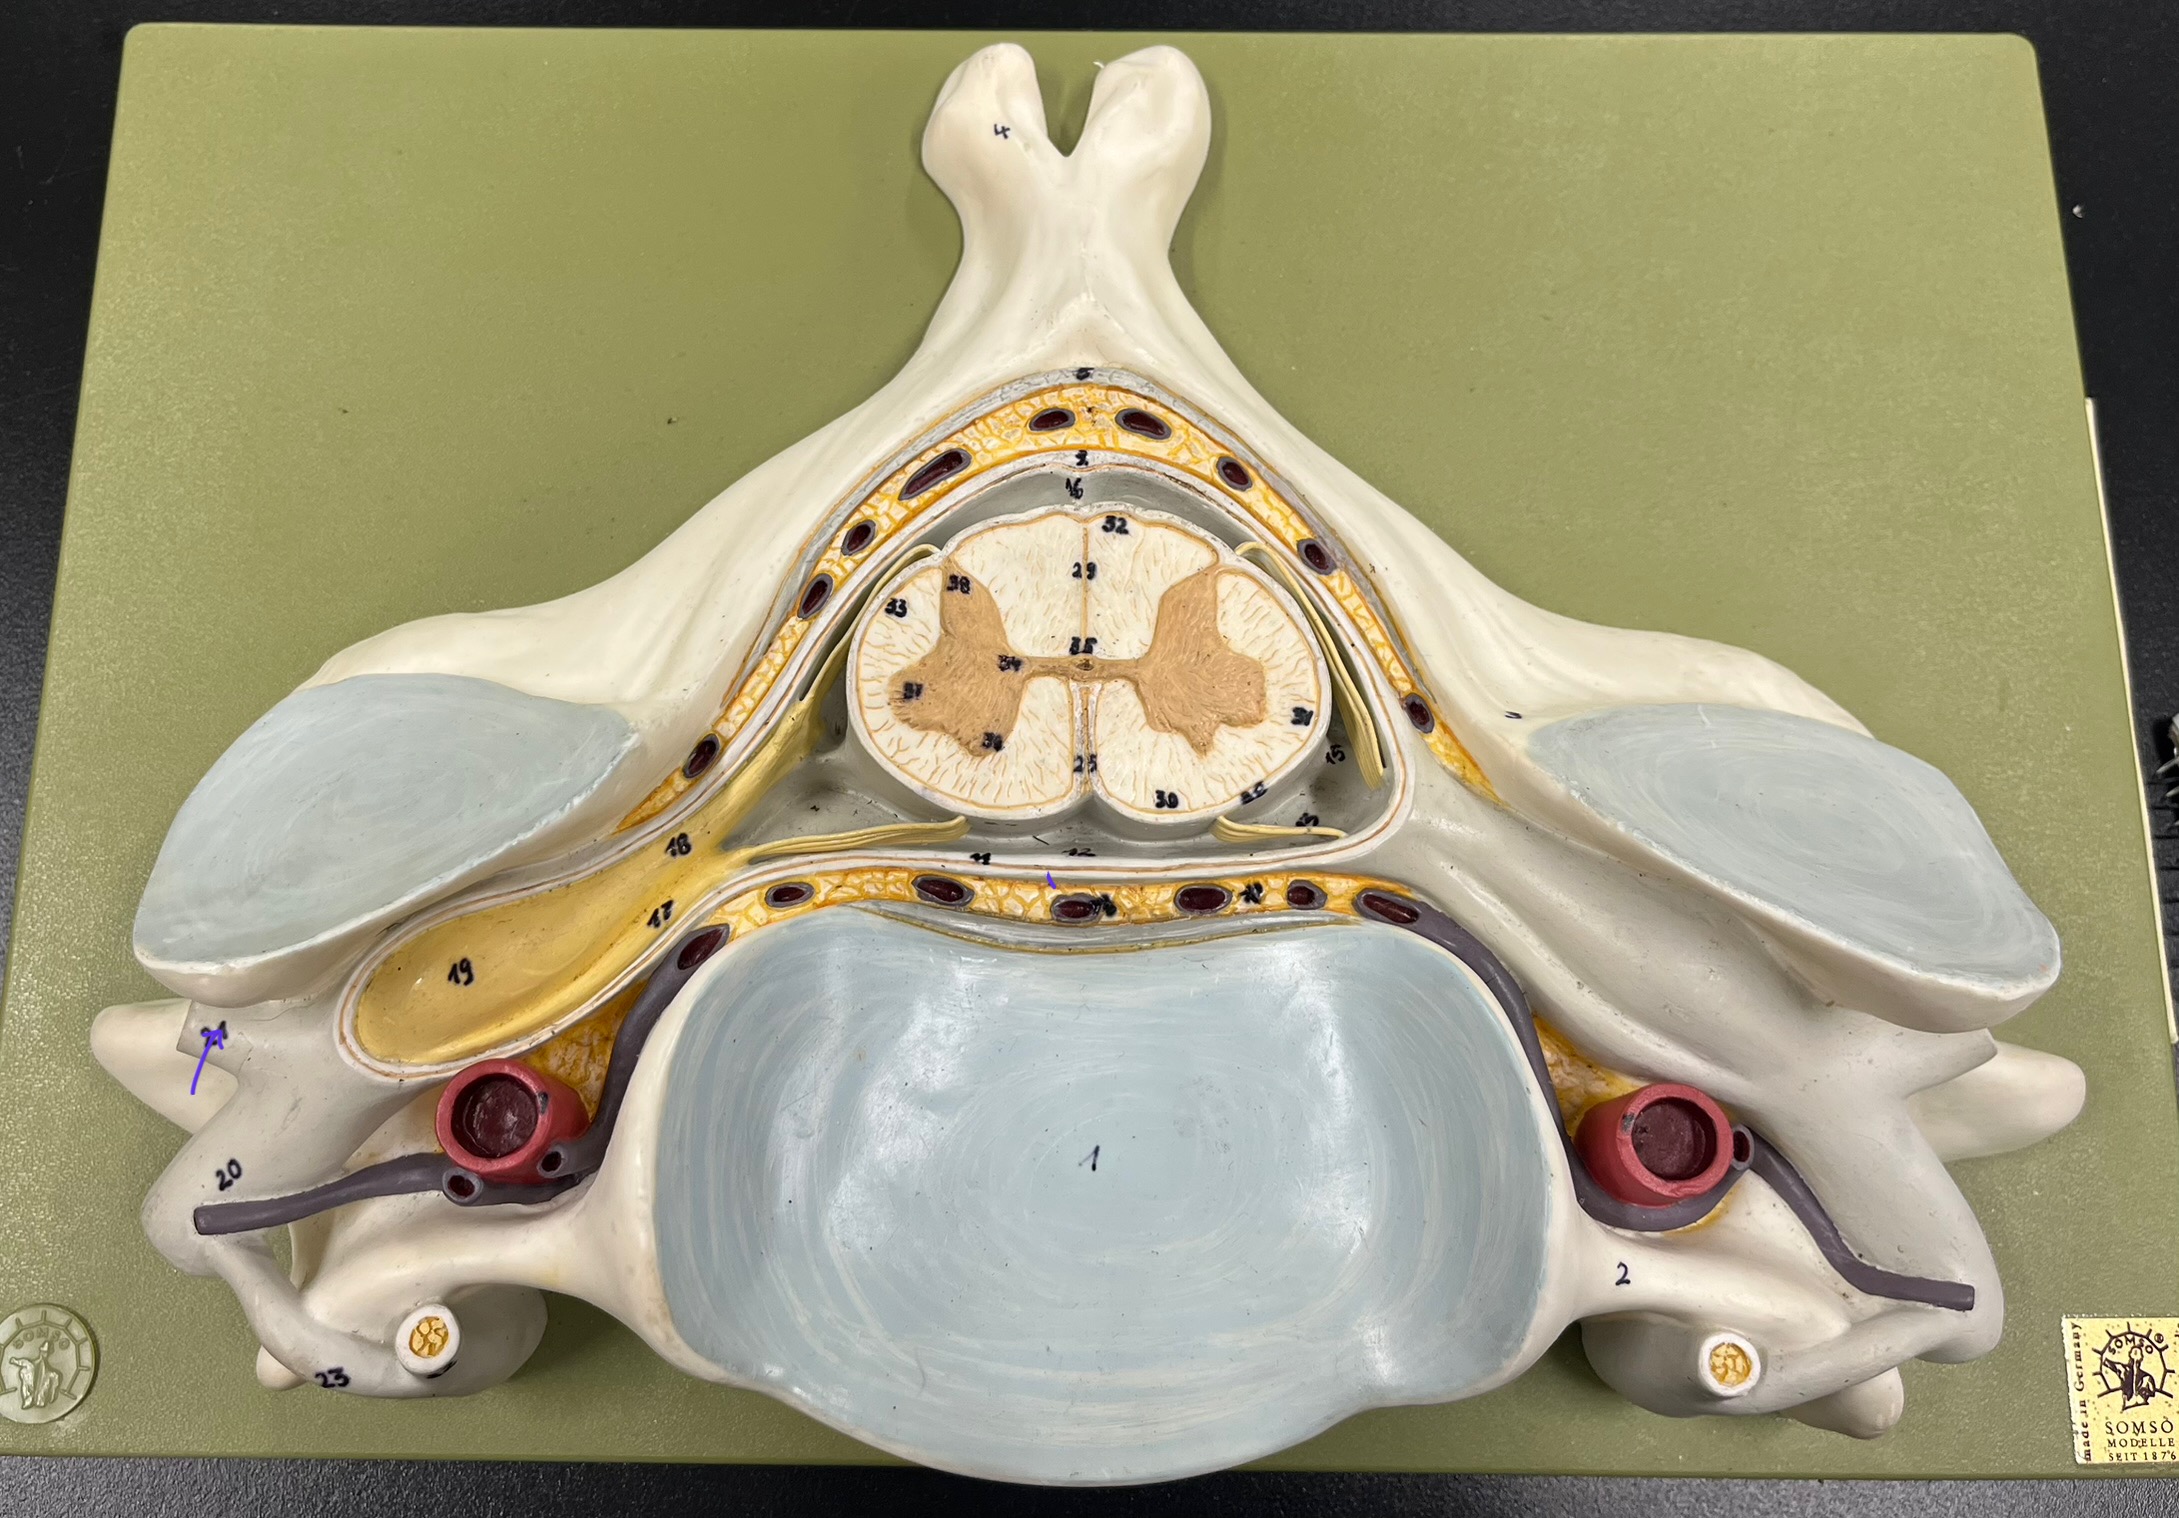

epidural space

dura mater

subdural space

arachnoid mater

subarachnoid space

pia mater

denticulate ligaments

What is the groove here?

anterior median fissure

posterior median sulcus

posterior (dorsal) horn

posterior (dorsal) horn; R—>L

anterior (ventral) horn

lateral horn (selected models)

gray commissure

central canal

anterior column

lateral column

posterior column

white commissure

posterior (dorsal) root ganglion

What is the bulb here?

posterior (dorsal) root ganglion

posterior (dorsal) root

posterior (dorsal) root

anterior (ventral) root

anterior (ventral) root

dorsal ramus

dorsal ramus

ventral ramus

ventral ramus

rami communicantes

rami communicantes

sympathetic chain ganglia

sympathetic chain ganglia